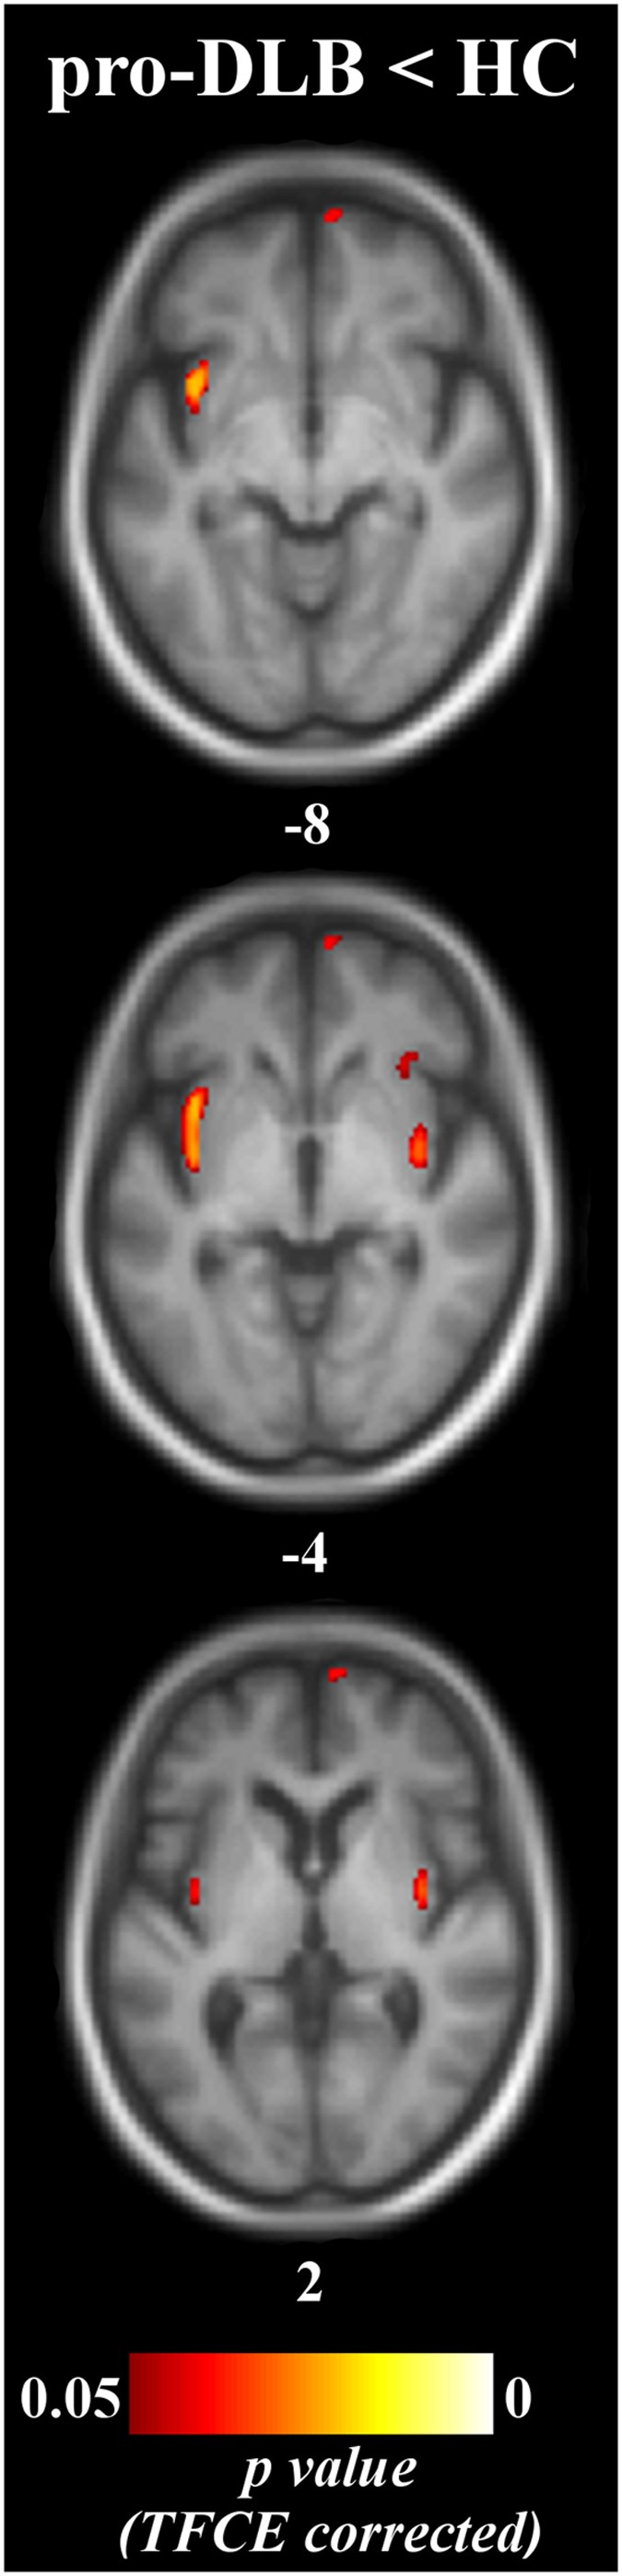

Unthresholded statistical images are freely available for consultation and download at http://neurovault.org/collections/2466 (the viewer has a threshold slider for which we recommend to set the left value to 0). Pro-DLB patients had a reduced GM volume in right medial frontal gyrus, and in bilateral insula and right claustrum relative to controls (Table 2, Fig. 1). Pro-AD patients did not differ from HC at p corrected < 0.05, although a tendency towards a GM loss in right hippocampus was observed at a lower statistical threshold (p corrected = 0.07 and p uncorrected = 0.0002). Comparisons between prodromal groups did not reveal any decrease of GM volume. Controls did not show any atrophy that exceeded that in prodromal patients. The effect of age did occur either in the insula or in the medial temporal lobe.

Patterns of significant gray matter loss across prodromal groups and healthy elderly controls pro-DLB, dementia with Lewy bodies at the prodromal stage; pro-AD, Alzheimer’s disease at the prodromal stage; HC, healthy controls. Results are expressed as p-values from permutation tests with threshold-free cluster enhancement corrected for multiple comparisons, and are superimposed on the mean MNI-standardized MRI T1-weighted image of the prodromal patients and healthy controls. Left is left side of the brain. Subscripts are the z-axis coordinates of the slice in the MNI space.